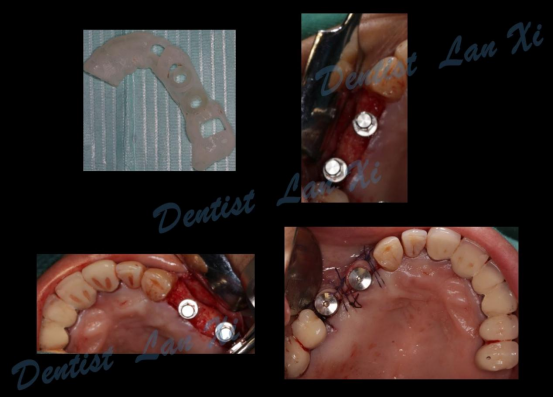

第四步:导板制作完成

(目前生成导板的方式主要有3D打印和切削两种方式)

第五步:外科手术

三、过程引导 更微创

数字化种植导板将术前设计方案精准转移,保证了种植体植入位置、方向及角度等的精确性,同时充分利用余留骨量,减少甚至避免了附加手术。